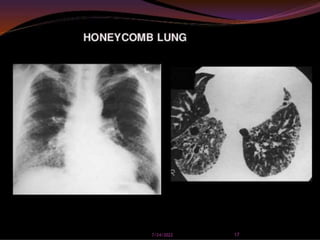

 Chest x-ray findings include small irregular

opacities, interstitial densities, ground glass

appearance, and honeycombing.